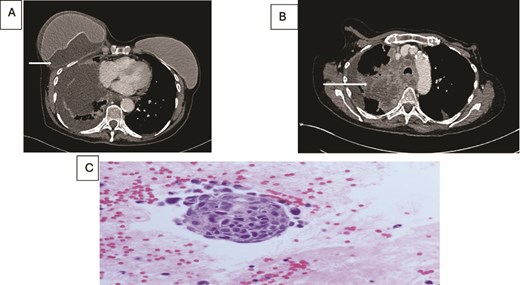

(A) Axial contrast enhanced CT scan shows heterogeneous lung mass with mediastinal invasion. (B) Axial CT image showing peri-implant malignant effusion. (C) fluid around breast implant: groups of atypical cells with hyperchromatic nuclei, high nuclear: cytoplasmic ratio and prominent nucleoli. The appearances are similar to the lung carcinoma diagnosed.

Concurrently she was being investigated for cough and weight loss with a CT scan which noted a right-sided pleural effusion and further fluid accumulation around the breast implant, as well as a right upper lobe lung lesion (Fig. 2). A biopsy of the lung lesion confirmed a poorly differentiated squamous cell carcinoma and further aspirations of the persistent right breast peri-prosthetic effusion revealed metastatic malignant cells consistent with a primary lung origin.